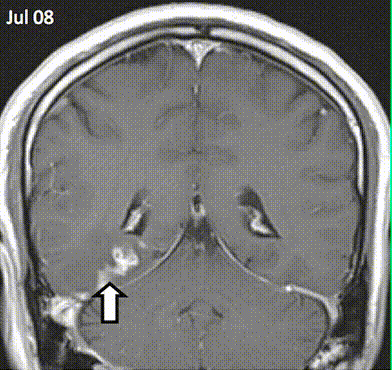

MRI yang menunjukkan cacing pita bergerak di otak manusia

Selama empat tahun ke depan, MRI lebih lanjut mencatat wilayah abnormal bergerak di otak manusia (lihat animasi), hingga akhirnya dokter memutuskan untuk melakukan operasi. Merekapun terkejut setelah menemukan cacing pita sepanjang 1 sentimeter.